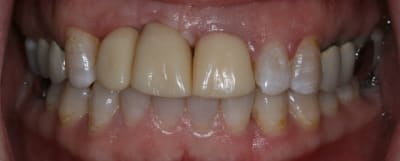

On avance dans le cas, j'ai revu la patiente hier.

Elle est satisfaite et moi pas vraiment, comme quoi...

Elle ne veut pas faire de chir mucco gingivale et accepte éventuellement que je fasse une petite chir d'élongation coronaire sur 21 car elle trouve cela surperflux.

Tristesse et difficulté des sourires gingivaux !

J'avais bien raison de me méfier au départ...

Dommage pour la teinte...

Une greffe osseuse aurait bcp aider, les implants sont trop enfouis par rapport à la 21.

Je suis persuadé que si ton prothèsiste réussit à reproduire la richesse des petits défauts de ses propres dents sur tes dents en céramique , ce serait et ça passerait bcp mieux

Je crois que finalement ces trois trop jaune et quasi monolithique ds leur couleur est vraiment la chose la plus atroce

Bon finalement je vous poste le cas terminé.

La prochaine fois je ferrai une greffe d'apposition comme j'avais pu le préssentir... Ca me permettra de garder les papilles.

Mon DuDule quel dommage que tu n'ai pas un ditramax car ta ligne interincisive n'est pas parallèle au plan médian et la ligne des bords libres pas parallèle à la ligne blanche masquant les yeux!